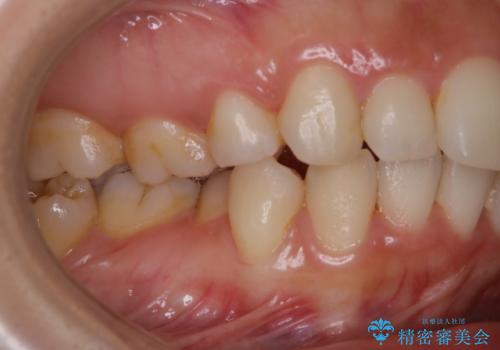

- しばらく来院できなかったため、全体的にチェックとクリーニング希望でした。PMTC60分コースを行いました。

歯にステイン(着色)や歯石などが付着していると、汚れなのか虫歯なのかの判別が分かりにくく、正確な診断ができないことがあります。

そのため、定期的に専門的な機械や材料を使用したクリーニング(PMTC)をすることで、ご自身本来の歯の状態となります。より、健康なお口の維持をするためには、痛みや症状などが無くてもPMTCを行いお口の中の環境を綺麗にすることがおすすめです。